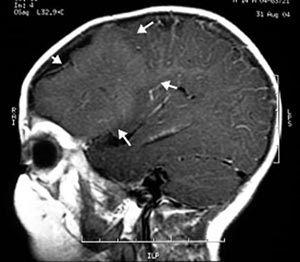

Figura 44 e 45 - Ressonância nuclear magnética realizada 3 meses após a cirurgia mostrando remoção adequada da lesão. Esse paciente permaneceu sem crises desde sua cirurgia realizada em 2005 e segue em acompanhamento médico, já sem medicação.